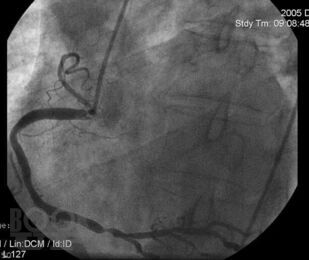

Chest Pain Syndrome

Chest Pain Syndrome : A textbook for students specializing in «General Medicine» / Н. Ш. Загидуллин, Д. Ф. Гареева, Е. А. Бадикова и др. - Уфа : БГМУ, 2024. - 72 c. - Текст : электронный // ЭБС "Букап" : [сайт]. - URL : https://www.books-up.ru/ru/book/chest-pain-syndrome-18216925/ (дата обращения: 02.05.2026). - Режим доступа : по подписке.

This textbook is developed in accordance with the Federal State Educational Standards of Higher Education (FSES HE) for the specialty 31.05.01 General Medicine (Moscow, 2020), the Basic Educational Program (BEP) for the specialty 31.05.01 General Medicine (2023), the curriculum (2023), and the course syllabus (2023) for students specializing in General Medicine. It is designed to facilitate the development of general professional competencies (GPC–4) and professional competencies (PC–5, PC–6) in accordance with the FSES.

This textbook presents modern knowledge of the basics of electrocardiography in cardiovascular diseases, necessary for students when studying the course «Propedeutics of Internal Diseases». The textbook also includes test tasks and situational problems of varying complexity for self assessment, with answer keys.